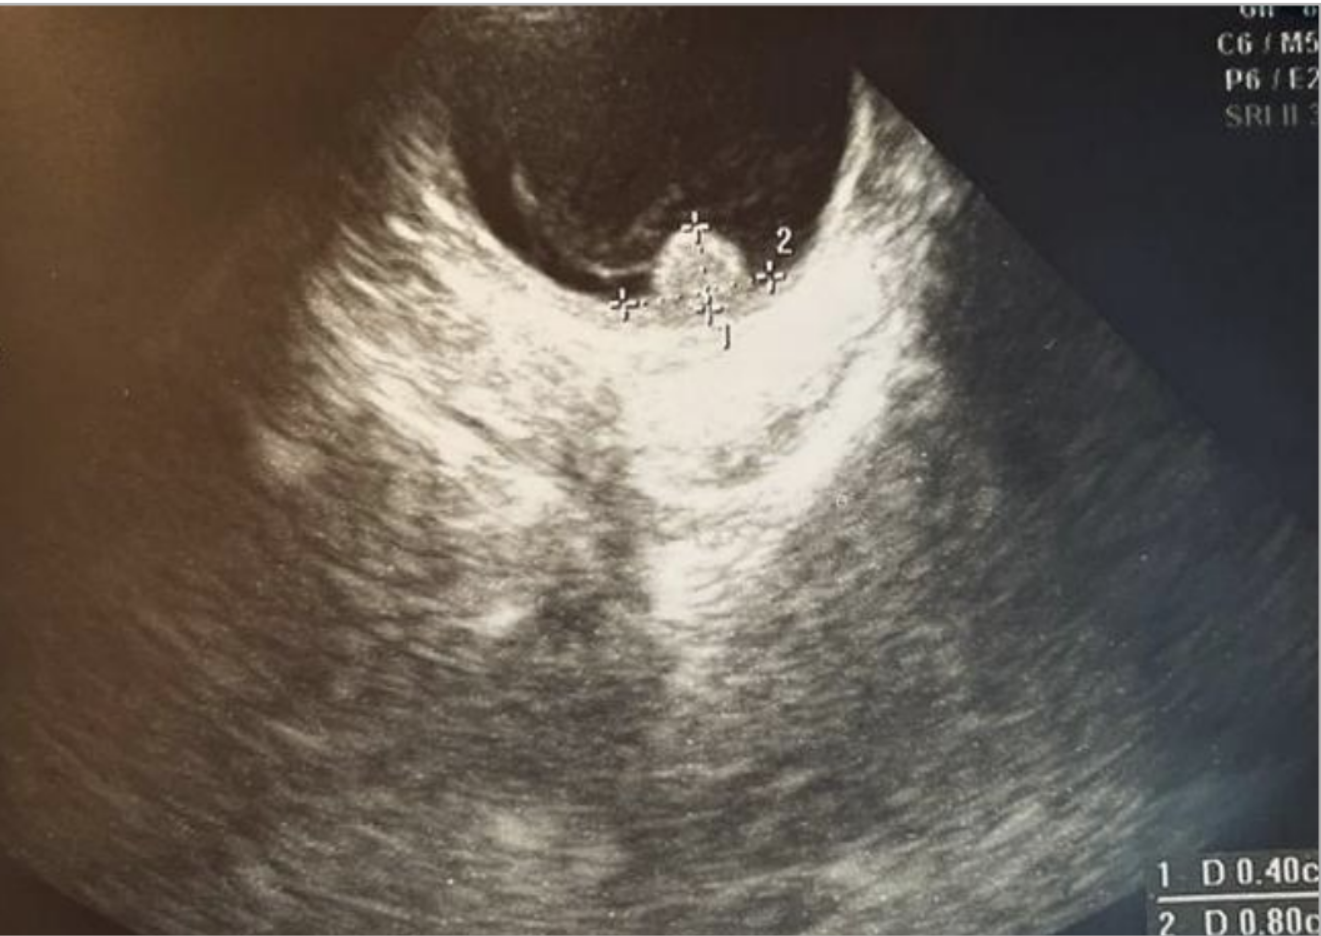

Валерия исследует физическую и эмоциональную трансформацию через призму личного опыта борьбы с заболеванием. Процесс исцеления и восстановления зрения становится метафорой внутреннего возрождения и смещения восприятия. Этот проект идеально дополнит тему выставки, так как он показывает, как болезнь меняет человека, но также и как он находит внутреннюю опору в новой реальности. Лера отражает путь от разрушения к восстановлению, создавая визуальный дневник своих переживаний.